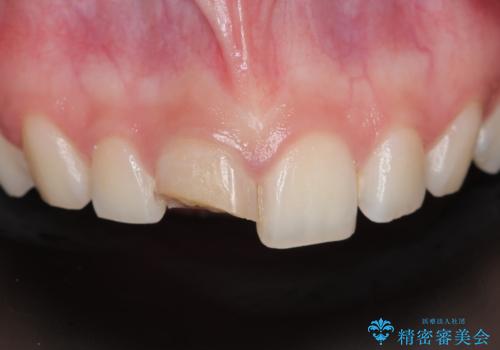

- 昔他院で虫歯治療をしたところが虫歯が再発したとのことで来院。

古い材料(プラスチックの樹脂)をとり、拡大鏡下で虫歯を全て取り除き、

ゴールドインレーにて治療しました。

歯の外側の面が少し欠けていて、そこの部分を覆う(ゴールドの範囲が広くなる)か

そこの欠けてる部分は虫歯ではないので削らないで、最小限にして詰め物を作るか相談したところ

欠けているところは何十年も昔から欠けていて特に何もない。なるべく歯を削りたくないとの事だったので

最小限で詰め物の治療をしました。